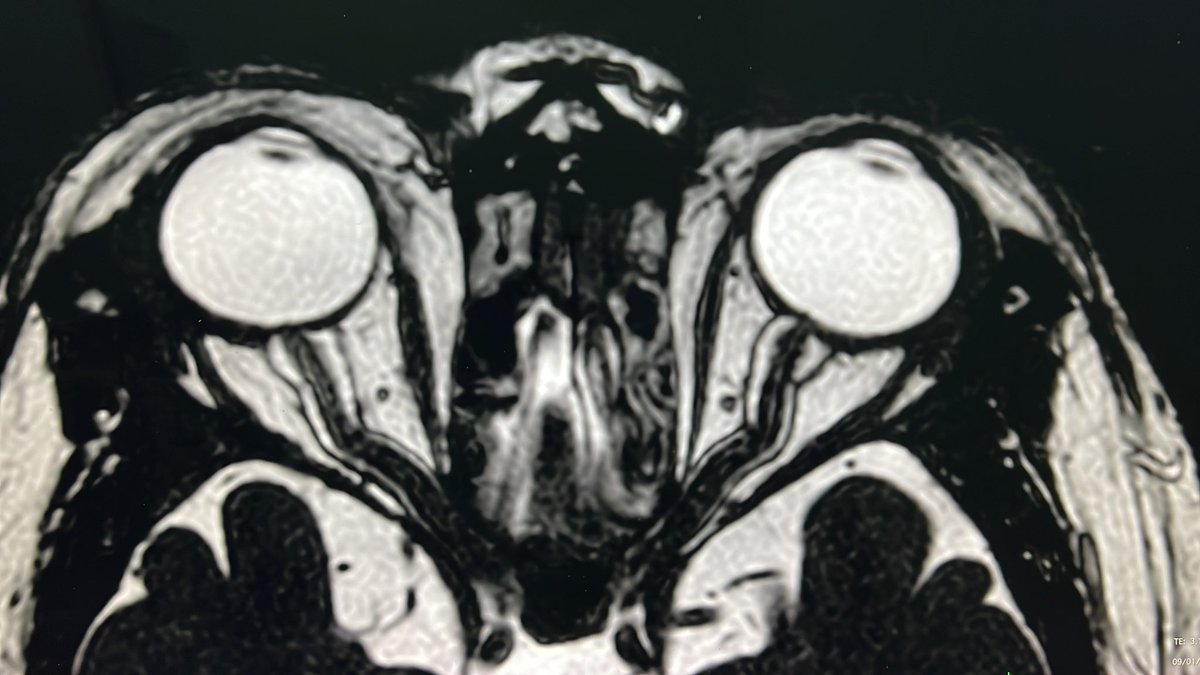

@drSurjthVattoth

Surjith Vattoth

11 months

Imaging Pearl 26: Ocular imaging: COLOBOMA versus STAPHYLOMA